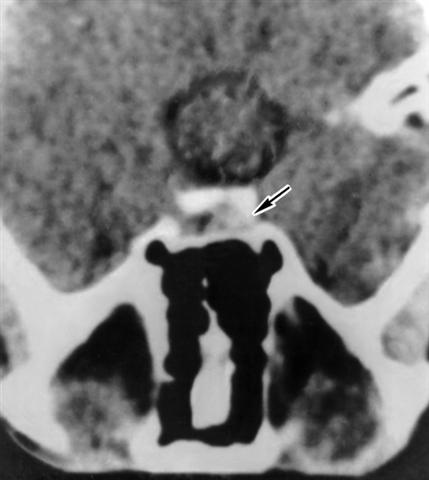

Рис. 2. Компьютерная томограмма области турецкого седла (аксиальная проекция) больного с соматотропиномой (указана стрелкой).